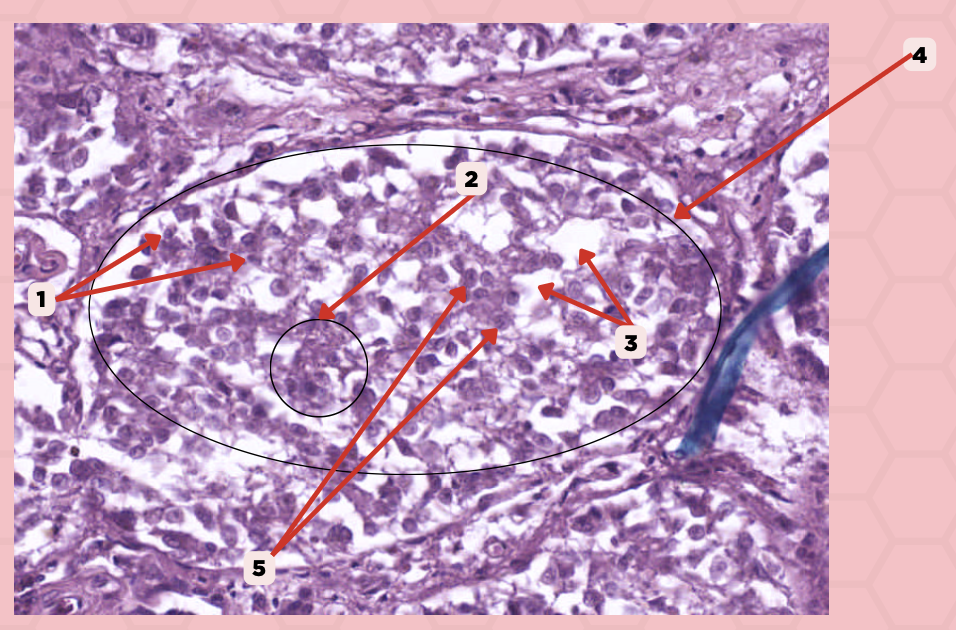

Pancreas

Identify the specimen.

Islets of Langerhans

Identify the structure labeled as 1.

Pancreatic Acini

Identify the structure labeled as 2.

Reticular Tissue

Identify the structure labeled as 3.

Beta-cells

Which cells occupy the central area of #1?

Pancreatic Acini

#3 delineates the pale- staining cells from the darker-staining cells. What do you call the darker-staining cells?